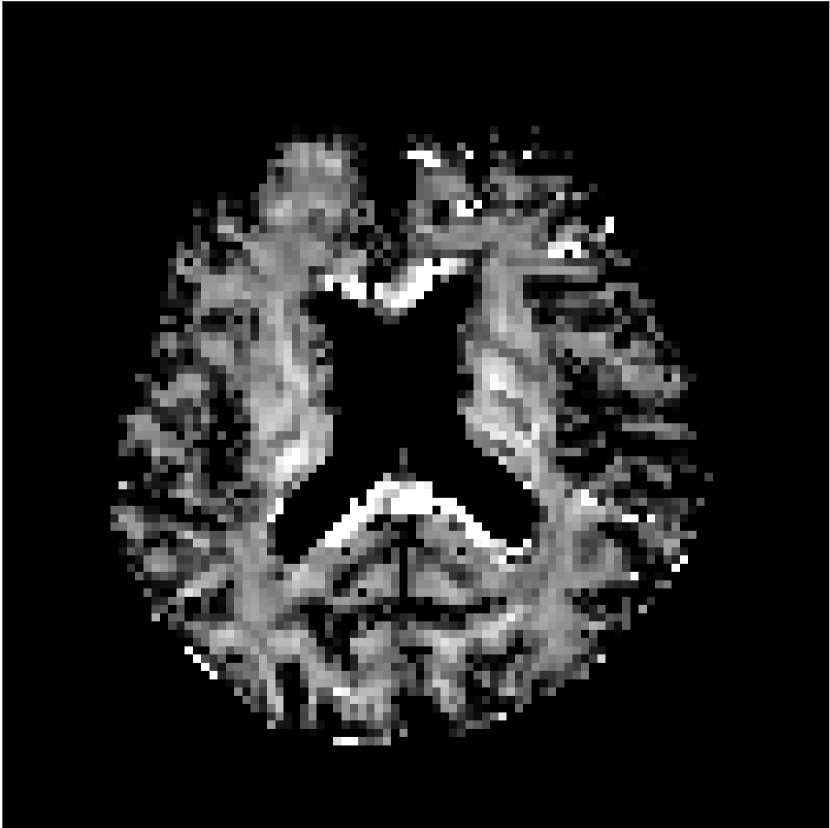

Figure 10 compares mean diffusivity maps across various partial Fourier factors between the CCNN and state-of-the-art methods.

No PF

7/8 PF

6/8 PF

5/8 PF

SoA

MD, m2/ms

CCNN

The methods perform similarly without partial Fourier acceleration, but as partial Fourier acceleration increases, the image is continually degraded in the SoA method, with "black voxels" appearing around the lateral ventricles. The CCNN method mitigates the appearance of these artifacts in the parameter maps.